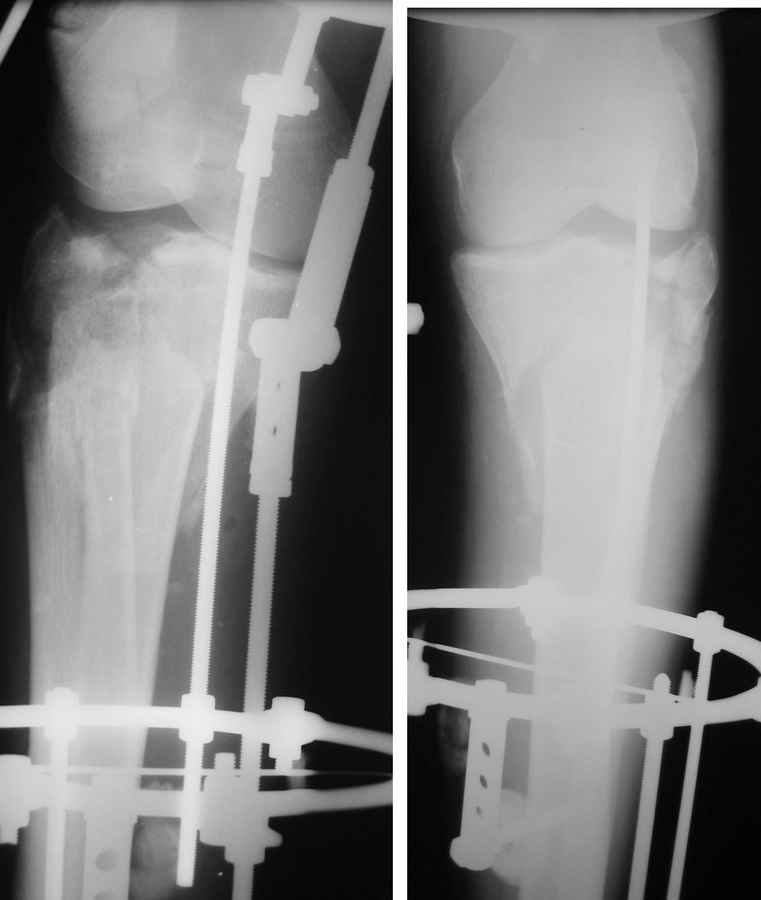

Состояние мягких тканей оказалось принципиальным в разработке плана операции.

Очаг некроза 4 на 5 см по передней поверхности голени не оставил никакого варианта кроме внешнего остеосинтеза.

Но решили делать в 2 этапа. Первый - восстановить ось и дать костной крошке в проксимальном отделе консолидироваться.

Второй - собственно артродез.

Но по результатам первого этапа думаем дать пациенту попользоваться ногой. А там посмотрим.

Для первого этапа достаточно. Через 5-10 дней мы бы приступили к следующему этапу. А именно, фиксация из ограниченного заднемедиального доступа 1\3 трубчатой или рекон пластиной медиального фрагмента, и остеосинтез наружного мыщелка из второго тоже ограниченного латерального доступа без артротомии, под контролем ЭОПа..... Сухой некроз в данном случае не являлся бы серьезной помехой для внутренней фиксации (во всяком случае, судя по имеющимся фото)

Оставляя внутрисуствной перелом в таком положении с замкнутым суставом, вы практически обрекаете пациента...IMHO

P.S. безусловно, с двумя пластинами LCP, каннюлироваными винтами, хроносом все это дорого... Но того же анатомического и функционального результата можно достичь, используя вместо пластин аппарат Илизарова, и разрезы для репозиции тогда нудны совсем маленькие .